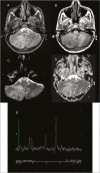

Figure 2

T2WI showing an irregular walled mass lesion with concentric/onion bulb like layers of hyper- and hypointensity in right cerebellar lobe with peri-lesional edema (A). On T1WI, the lesion appears predominantly isointense with a thin peripheral hyperintense rim and a focus of central hypointensity (B). DWI and ADC images show no restriction (C and D). MRS image shows a distinct lipid peak (E)